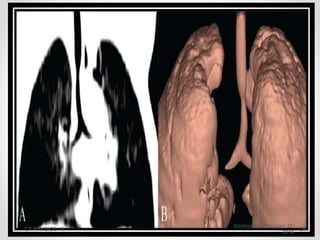

• Transverse images are stacked to form a 3 D data set ,which can

be rendered as an image .

• Mostly used in Multispiral CT

• The algorithms include –

(i) Maximum Intensity projection (MIP)

(ii) Minimum Intensity Projection ( MinIP)

(iii) Surface shaded display volume rendering technique.

MULTIPLANAR RECONSTRUCTION

• Transverse imagesare stacked to form a 3 D data set ,which can be rendered as an image . • Mostly used in Multispiral CT • The algorithms include – (i) Maximum Intensity projection (MIP) (ii) Minimum Intensity Projection ( MinIP) (iii) Surface shaded display volume rendering technique. MULTIPLANAR RECONSTRUCTION Wednesday, February 10, 2016 CT PHYSICS - II 21

• #22 Simplest form of 3D imaging and widely used in CT angiogram . Differeniated vascular from surrounding tissue but lacks vessel depth . MIP MIP is a data visualization method that enables detection of highly intense structures. The algorithm uses all the data in a volume of interest to generate a single bidimensional image structures, such as vessels, nodules, calcifications, surgical clips, foreign bodies, etc., and detect small lung nodules, [5],[6] which can easily be distinguished from other dense structures in the lungs, with the air present in the alveoli acting as a natural contrast agent. MinIP data visualization method that enables detection of low-density structures in a given volume. uses all the data in a volume of interest to generate a single bidimensional image. [3] almost identical to the MIP algorithm but for each XY coordinate only the lowest Hounsfield value along the Z axis is represented. only the most hypodense structures of the volume are represented Mapping of the thorax before administration of contrast, an image of the bronchial tree can be generated since the bronchi, being air-filled, are the least dense structures of the thorax SVD makes the surface boundaries very distinct and provides an image that appears exact 3D.

• #23  MIP MIP is a data visualization method that enables detection of highly intense structures. The algorithm uses all the data in a volume of interest to generate a single bidimensional image this reconstruction algorithm is used with data representing the thorax during the arterial contrast phase, a single image with all the arterial vessels present in the volume studied is generated. Better understand the extension and morphology of some structures, such as vessels, nodules, calcifications, surgical clips, foreign bodies, etc., and detect small lung nodules, [5],[6] which can easily be distinguished from other dense structures in the lungs, with the air present in the alveoli acting as a natural contrast agent. MinIP data visualization method that enables detection of low-density structures in a given volume. uses all the data in a volume of interest to generate a single bidimensional image. [3] almost identical to the MIP algorithm but for each XY coordinate only the lowest Hounsfield value along the Z axis is represented. only the most hypodense structures of the volume are represented Mapping of the thorax before administration of contrast, an image of the bronchial tree can be generated since the bronchi, being air-filled, are the least dense structures of the thorax SVD makes the surface boundaries very distinct and provides an image that appears exact 3D.

• #25  MinIP data visualization method that enables detection of low-density structures in a given volume. uses all the data in a volume of interest to generate a single bidimensional image. [3] almost identical to the MIP algorithm but for each XY coordinate only the lowest Hounsfield value along the Z axis is represented. only the most hypodense structures of the volume are represented Mapping of the thorax before administration of contrast, an image of the bronchial tree can be generated since the bronchi, being air-filled, are the least dense structures of the thorax SVD makes the surface boundaries very distinct and provides an image that appears exact 3D.